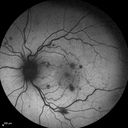

33 year old He noticed a new flash in the left eye. The flash started about 2 hours prior to the photos and he still notices it. The flash is in the center of the vision. The vision is not blurred. It's hard to tell because of the dilation. VA 20/12 OD and 5/200 OS. The vision remarkably improved to 20/16 within 1 month in the left eye. Blood tests showed a protein C deficiency.

Central retinal artery and vein occlusion - Protein C Deficiency 33 year old male406 views33 year old male with vision loss for 3 hours. VA 20/12 right eye, 5/200 left eye. He has a protein C deficiency. The left eye recovered vision in about 1 month to 20/16. FA shows very slow recirculation time.     (0 votes)